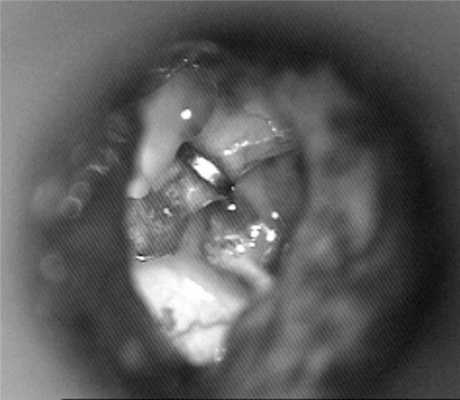

Пациентке А. в одной из больниц Нижнего Новгорода в 2011 г. была выполнена поршневая стапедопластика металлическим протезом с тефлоновой ножкой на левом ухе по поводу смешанной формы отосклероза с положительным морфофункциональным результатом (рис. 1). Рисунок 1. Функциональный результат стапедопластики на левом ухе.

Протез был удален, после чего пациентка уже на операционном столе отметила значительное уменьшение головокружения. Спайки в области овального окна были рассечены, лентикулярный отросток наковальни отведен латерально. В имеющееся отверстие в нише овального окна был установлен титановый протез К-пистон минимального размера 4,0 мм (рис. 5). Рисунок 5. Интраоперационное фото. Установлен протез К-пистон 4,0 мм. Послеоперационный период протекал спокойно. Пациентка была повторно консультирована сурдологом и отоневрологом. Отмечен регресс горизонтального спонтанного нистагма вправо. Выписана с улучшением на 7-е сутки после операции.